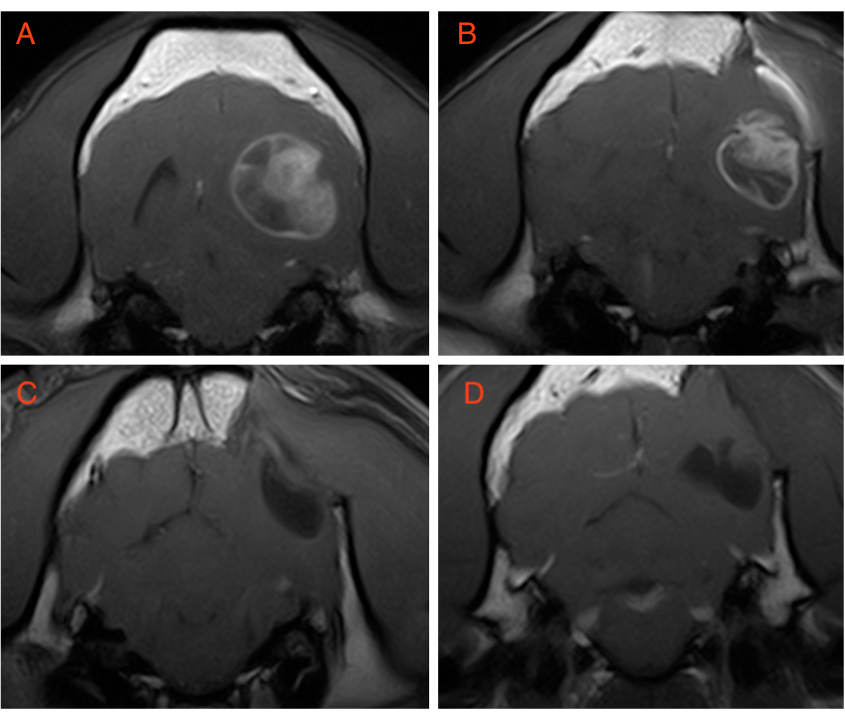

A 5-year-old male neutered French Bulldog presented for an onset of cluster seizure activity. The neurological examination was considered normal at the time of presentation. Otherwise considered healthy, the dog underwent a brain MRI using the Hallmarq 1.5T machine (Fig. 1).

Based on these images supporting a suspected diagnosis of an intracranial glioma, a craniectomy for mass resection was performed, which confirmed an astrocytoma. The surgery was followed by stereotactic radiotherapy 3 weeks later. Repeat imaging was undertaken 2 weeks after the surgery (Figures 2B & 3B), 6 months after the radiotherapy (Figures 2C & 3C), and 1 year after the radiotherapy (Figures 2D & 3D).

Figure 1. Transverse MR images at the level of the occipital lobes at the time of the dog’s initial presentation. (A) T2W; (B) FLAIR; (C) T1W; and (D) T2* sequences. A large, ill-defined and multi-compartmental intraparenchymal lesion is seen at the level of the occipital lobe on the left side. The lateral component of the lesion is heterogeneously T2W, T2*, and FLAIR hyperintense to grey matter with irregular intralesional hypointensities on all sequences.

The medial portion of the mass is more well-defined with a distinct fluid line near its dorsal aspect. The ventral portion is homogeneously hyperintense on all sequences apart from being mildly hypointense on T1W. The dorsal aspect is hypointense on T2W and FLAIR, mildly hypointense on T1W with mixed to hyperintense signal on T2*. This medial portion represents a highly proteinaceous cystic component with suspected dorsal haemorrhage. The main differentials for this mass lesion would include high-grade glioma and, less likely, an inflammatory granuloma.

Figure 2. Transverse T2W images at the level of the occipital lobes acquired at the time of presentation (A), 2 weeks after surgery (B), 6 months after surgery and radiation therapy (C), and 1 year after surgery and radiation therapy (D). The bone defect in the overlying calvaria secondary to surgery can be seen (arrow). The soft tissue lateral mass is smaller post-surgery, but is not detectable after radiation. A cystic lesion remains after radiation (C & D).